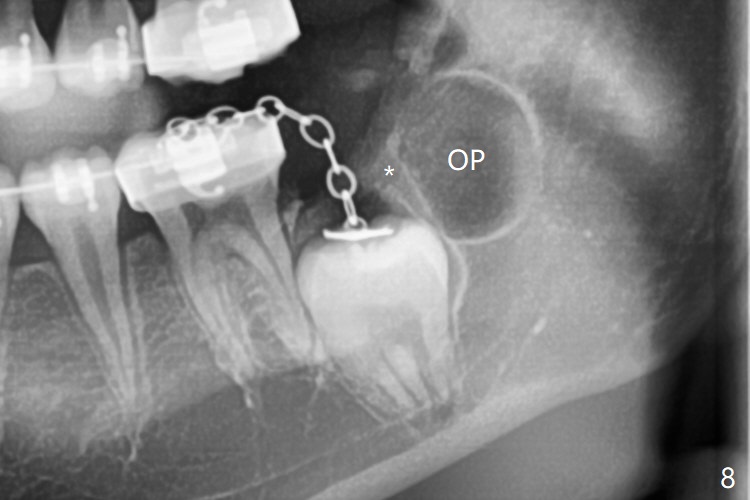

Treatment planning of surgical access to the impacted 7 (Fig.1) before CT analysis (to be canceled due to finance) include extraction of 8 (Fig.2) and removal of the bone coronal to 8 (Fig.3 red) so that there will be no bony block to 7 eruption (Fig.4). Place PRF or collagen plug in 8 socket to facilitate healing (Fig.3). Attach a retraction chain to the occlusal or buccal surface of 7 (Fig.6 pink) whenever it is convenient in term of hemorrhage and access (as mesial as possible). Remove 16 niti wires for brushing when the patient arrives. Cut 18 ss wire longer in the LL end (Fig.6 green to be bent to hook power chain (yellow)). Incision is shown as red in Fig.5. After 3 month delay, the thick buccal plate is removed from LL8 (1st) and 7 (2nd in sequence, as compared to Fig.2) to expose these unerupted teeth. In fact CT is not taken to decrease budget on the divorcing parents. A retraction chain is placed before extraction of LL8 with an intention to reduce hemorrhage (Fig.7). Although extraction requires several sectioning of the tooth, hemorrhage is mild to moderate. Instead of PRF and sticky bone (as compared to Fig.3), Osteogen plug is placed in the socket (Fig.8 OP). The bony septum between the 2 sockets is intentionally kept in place (*). 事实的确这样发生(图九:*)。埋伏牙不仅上移(^),而且远中移动(>),因为牵引方向(红虚线(橡皮筋),挂在上牙弓丝(图九:20ss:图十:18ss(之前))远端勾,积极牵引三个星期)。下次左上7放置舌侧纽扣,让病人更换橡皮筋。其实纽扣粘不住,上牙弓丝远中勾也不现实,只能使用橡皮筋挂在左上6,经常断。术后6个月,左下7继续上移(图十一)。这种低效率牵引仍然有效,牙齿继续上移,牙根长长(图十二:空箭头),但是受到左下6远中阻挡(*),所以下次在左上7咬合面装置舌侧纽扣和closed spring,改善牵拉方向(红箭头)。